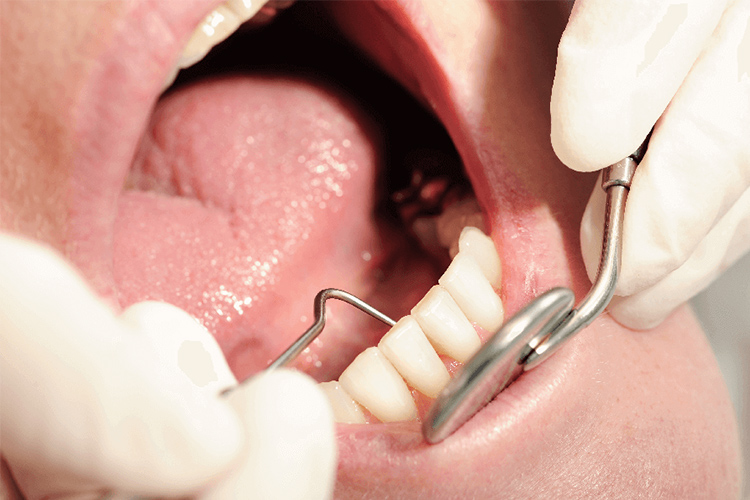

予防治療

歯周病は、歯の支えとなる部分の骨を溜まった汚れや歯石が溶かしてしまう病気です。

虫歯と並んで歯を失う原因の一つとなっている歯周病ですが、その治療にはプラーク(歯垢)を取り除き、歯肉、歯根膜などの歯周組織の炎症を抑えることが有効となっています。

原因を取り除くことで再発の予防もしていきます。

細菌を歯周ポケットから除去することで、歯周組織の健康は維持できますが一度歯周組織を失ってしまうと、自然に元に戻ることはありませんので適切な治療をすることが大切です。

PMTC(プロフェッショナル・メカニカル・ティース・クリーニング)

普段の歯磨きでは難しい歯と歯の隙間や、口腔内の隅々を専用の機器を使用してケアします。歯磨きだけでは落としきれない汚れや歯垢の元になるバイオフィルムも除去します。

PMTCは歯周病改善だけでなく虫歯も防ぎ、歯質強化、着色除去して光沢感を出す効果もあります。